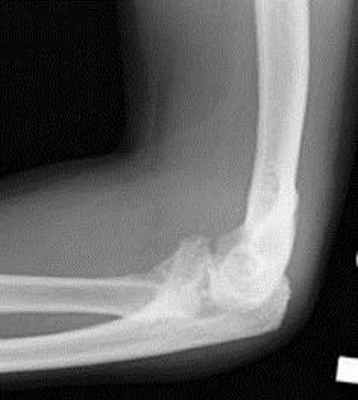

Перелом локтевого отростка • Причины: прямая травма, резкое сокращение трёхглавой мышцы плеча • Клиническая картина: припухлость локтевого сустава, рука выпрямлена, свисает; пассивные движения причиняют боль, активное разгибание при переломе со смещением невозможно, треугольник Хютера деформирован, вершина локтевого отростка находится выше линии, соединяющей надмыщелки плеча • Лечение •• Переломы без смещения: гипсовая повязка на 3–4 нед в положении сгибания предплечья в локтевом суставе на 90–110°, в среднем положении между пронацией и супинацией •• Перелом со смещением более 5 мм — остеосинтез •• ЛФК.